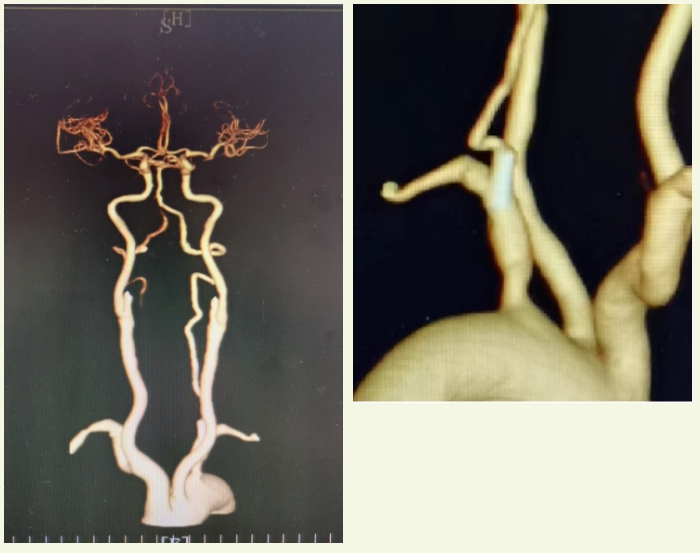

术后复查CTA

手术伊始,神经内科团队运用经股动脉入路脑血管造影技术(DSA),从股动脉插入特殊导管并注入造影剂,清晰呈现血管状况。通路建立后,用微导丝、6F鞘等将2.5×12mm球囊送至闭塞段,采用基底动脉球囊扩张技术对狭窄部位进行两次扩张,同时整合了SWIM技术,放置支架抓取血栓并配合导管抽吸取栓,成功清除大部分血栓。

第一次抽吸后,虽然大部分血栓被成功清除,但血管内的情况发生了变化,血管壁褶皱、分支处可能还隐藏着残余血栓。若不彻底清除,会持续影响血管的正常供血,导致患者病情反复,甚至再次危及生命。神经内科团队决定采用二次抽吸技术,迅速依据实时造影迅速判断残余血栓情况,在已操作过的血管内进行第二次抽吸,精准吸出8cm血栓。

江顺福表示,完成抽吸后造影发现基底动脉下段仍存在问题,遂利用同轴输送技术成功植入椎动脉支架,解决血管狭窄问题,历时1.5小时,顺利完成手术。